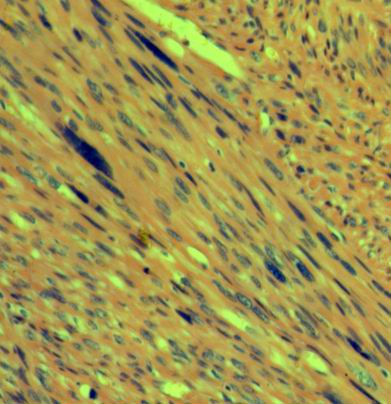

外生殖区平滑肌肿瘤如果诊断平滑肌肉瘤,需把握如下建议的恶性标准((Tavassoli,1979 和Norris, 1979):

需满足下列三个或三个以上条件

(1)肿瘤直径大于5cm;

(2)肿瘤边缘可见侵袭性生长;

(3)核分裂计数大于5个/10HPF;

(4)瘤细胞显示的异型性达到中-高度。

Norris 和Fletcher指出,如果肿瘤内可见凝固性坏死(肿瘤性坏死),只要满足上述四个条件中的任何一条,诊断平滑肌肉瘤将由可能。

外阴部平滑肌肉瘤在男性好发于睾丸、阴茎、精索。在女性,好发于外阴和阴道。

当不能满足上述条件,而具有以下情形的,可诊断为非典型性平滑肌肿瘤(WHO分类将称之为平滑肌肿瘤恶性潜能未定):

(1)肿瘤向边界呈侵袭性生长;

(2)肿瘤细胞具有异型性;

(3)可见核分裂,但核分裂计数达不到上述诊断肉瘤的标准。

本例如果达不到肉瘤标准,可考虑诊断为非典型性平滑肌肿瘤或平滑肌肿瘤恶性潜能未定。